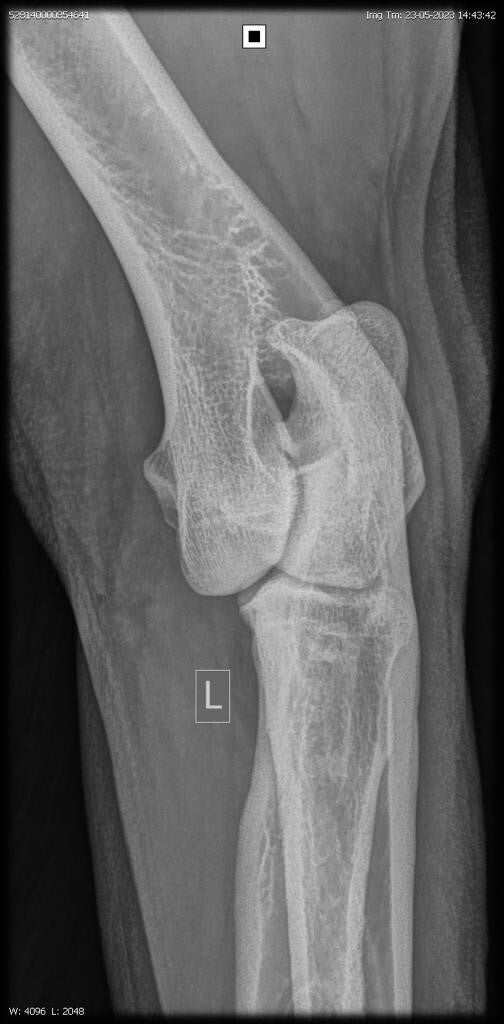

23/06/2023: Röntgenopname ellenbogen + heupen -> geen afwijkingen (heupdysplasie A, ED vrij)